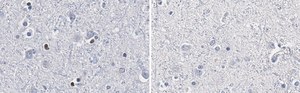

Immunohistochemistry (Paraffin) Analysis: A 1:100 dilution from a representative lot detected Olig2 in human cerebral cortex tissue sections.